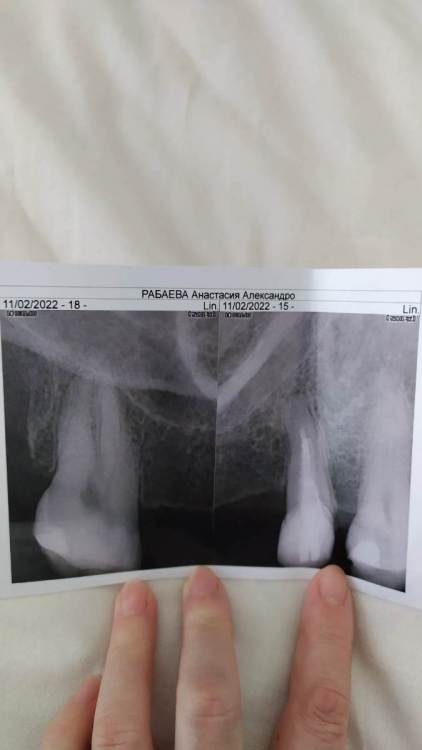

Рабин Опубликовано 5 февраля, 2022 Поделиться Опубликовано 5 февраля, 2022 (изменено) Уважаемые врачи! Помогите с принятием решения по поводу моста 15-17 зубов, насколько 15 и 17 зубы подходят под опорные зубы для моста. И есть ли имплантата костные условия, если на 16 ставить имплант? И как в целом выглядят зубы на панорамном снимке, есть ли кариозные полости? Прилагаю также прицельный снимок 15 зуба, насколько правильно пролечены каналы? Спасибо! https://drive.google.com/file/d/1c4v5cu_EYlkAKxlvgJct0VTgjlZmsbj2/view?usp=drivesdk https://drive.google.com/file/d/1ZcBxGcBZ8exDA28CTN1Y1ocpQ1TEEYoX/view?usp=drivesdk Изменено 5 февраля, 2022 пользователем Рабин Ссылка на комментарий

Рабин Опубликовано 12 февраля, 2022 Автор Поделиться Опубликовано 12 февраля, 2022 Спасибо за ответ! А под мостовидный протез подходят 15 и 17 зубы? Спасибо! Прилагаю прицельный снимок 15 зуба после перелечивания его от кариеса и поменяли также штифт анкерный на более современный. Ссылка на комментарий

Рабин Опубликовано 12 февраля, 2022 Автор Поделиться Опубликовано 12 февраля, 2022 07.02.2022 в 16:29, Карен Аванесов сказал: Идеальные условия для имплантации, мою догадку подтвердит КЛКТ. И в целом все пока неплохо. Спасибо за ответ! Компьютерную томографию не обязательно делать? И скажите подходят ли 15 и 17 зубы под опорные под мост? Прилагаю прицельный снимок 15 зуба после перелечивания ( убрали кариес и поменяли штифт анкерный на более современный) спасибо! Ссылка на комментарий